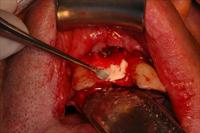

![]() 5. A transposition flap was performed and the site closed with a tension free series of simple interrupted polyglactin 910 sutures. |

![]() 6. View of prepared bony ridge. |